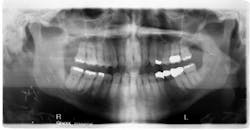

After this surgery, our patient felt much relief and had an amazing ability to accommodate using only his left side to chew. The only area of pain came from his now-displaced coronoid process, which was pushing into the approximate area of the maxilla. Unfortunately, the draining fistula would not go away. The patient was treated with several rounds of antibiotics, multiple visits to aBy the spring of 2018, the ORNJ had returned. Another surgery was performed. Another tooth was removed (no. 29), along with more bone.

Thankfully, this time surgery was a success. The fistula is gone, and there have been no new ulcerated lesions to date (figure 3).